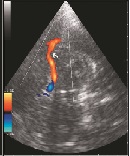

Ultrasonographic Characteristics of Carotid and Middle Cerebral Arteries in Patients with Ischemic Stroke

Rizvan Yagubovich Abdullaiev1*, Alexandra V. Kogut1, Irina A. Hryhorova2, Olena L. Tovazhnyanska2, Nicolay F. Posokhov3, Olga V. Markovska2, Olga A. Teslenko2